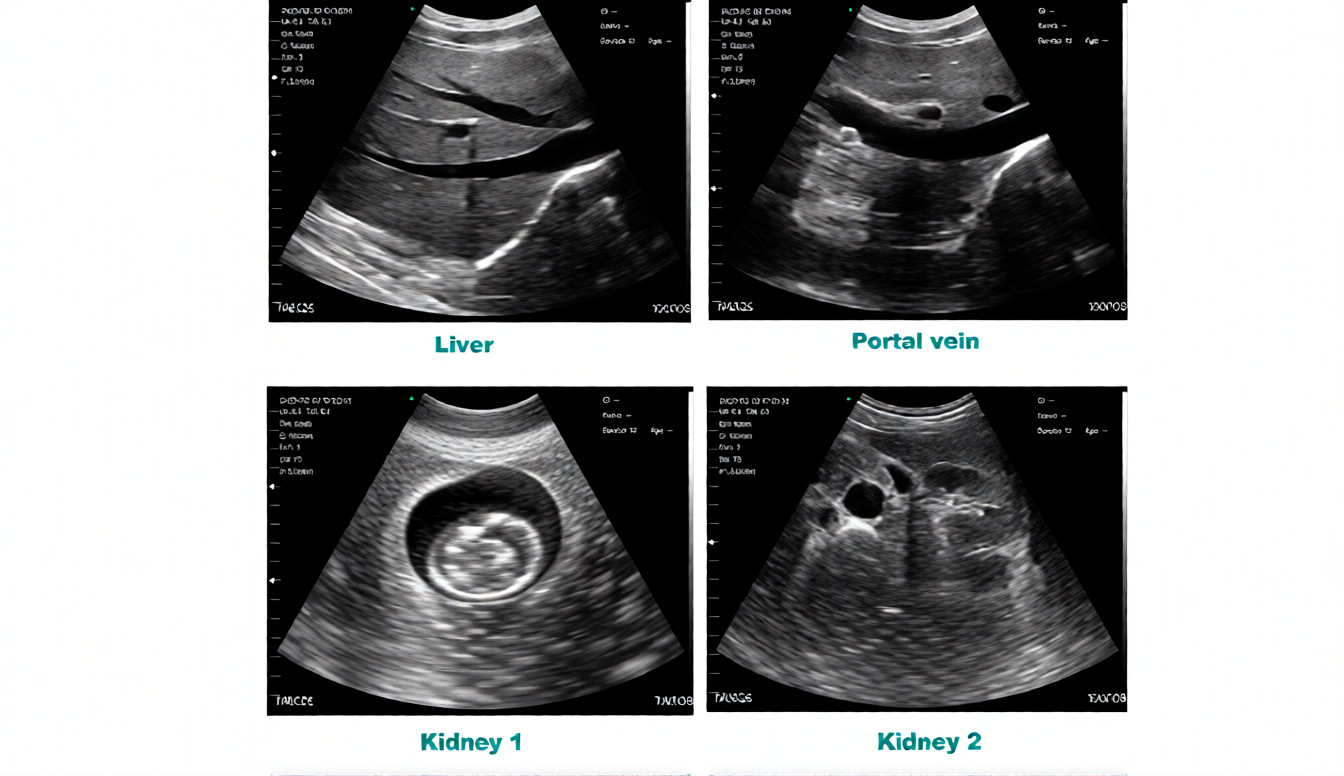

The SonoSmart Wireless Ultrasound Probe Convex-64C is a next-generation diagnostic equipment solution developed for fast, accurate, and mobile ultrasound imaging. Designed with advanced wireless technology, this probe connects seamlessly to smartphones, tablets, or computers, making it ideal for hospital equipment, medical equipment, and OT equipment use.

Manufactured in China, the Convex-64C model ensures stable performance, strong penetration, and clear imaging for abdominal, OB/GYN, and general diagnostic applications. Its lightweight and cable-free design allow doctors and technicians to perform scans anywhere—emergency rooms, ICUs, operation theaters, and even remote locations.

The SonoSmart Convex-64C Wireless Ultrasound Probe is a portable diagnostic imaging device designed for professional medical use. It delivers clear ultrasound images through wireless connectivity, making it suitable for hospitals, diagnostic centers, and clinics seeking reliable and affordable medical equipment in Bangladesh.

This wireless ultrasound probe is used for abdominal, OB/GYN, and general diagnostic examinations. Doctors and technicians can perform quick scans in hospitals, operation theaters, emergency units, and clinics. Its wireless design allows easy movement and fast diagnosis with minimal setup time.

Convex probe design for deep scanning

High-resolution diagnostic imaging